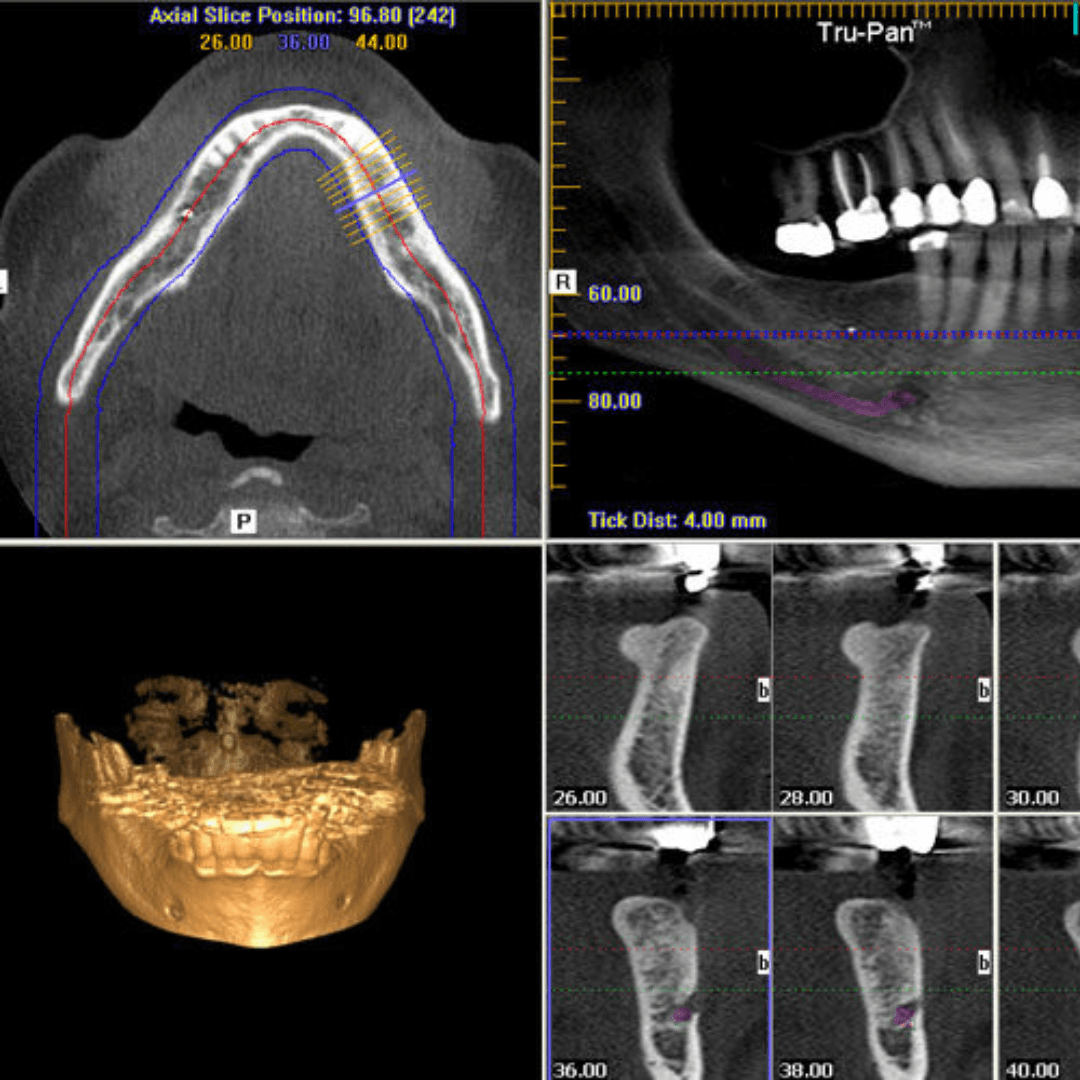

If your dentist needs 3D (CBCT)

An OPG is an overview. For detailed 3D planning (implants, sinus lift planning, or detailed nerve assessment), your dentist may request a CBCT scan. See our internal page: 3D scans (CBCT).

If your dentist specifically needs 3D imaging for implants / sinus lift / detailed nerve assessment, see: 3D scans (CBCT).